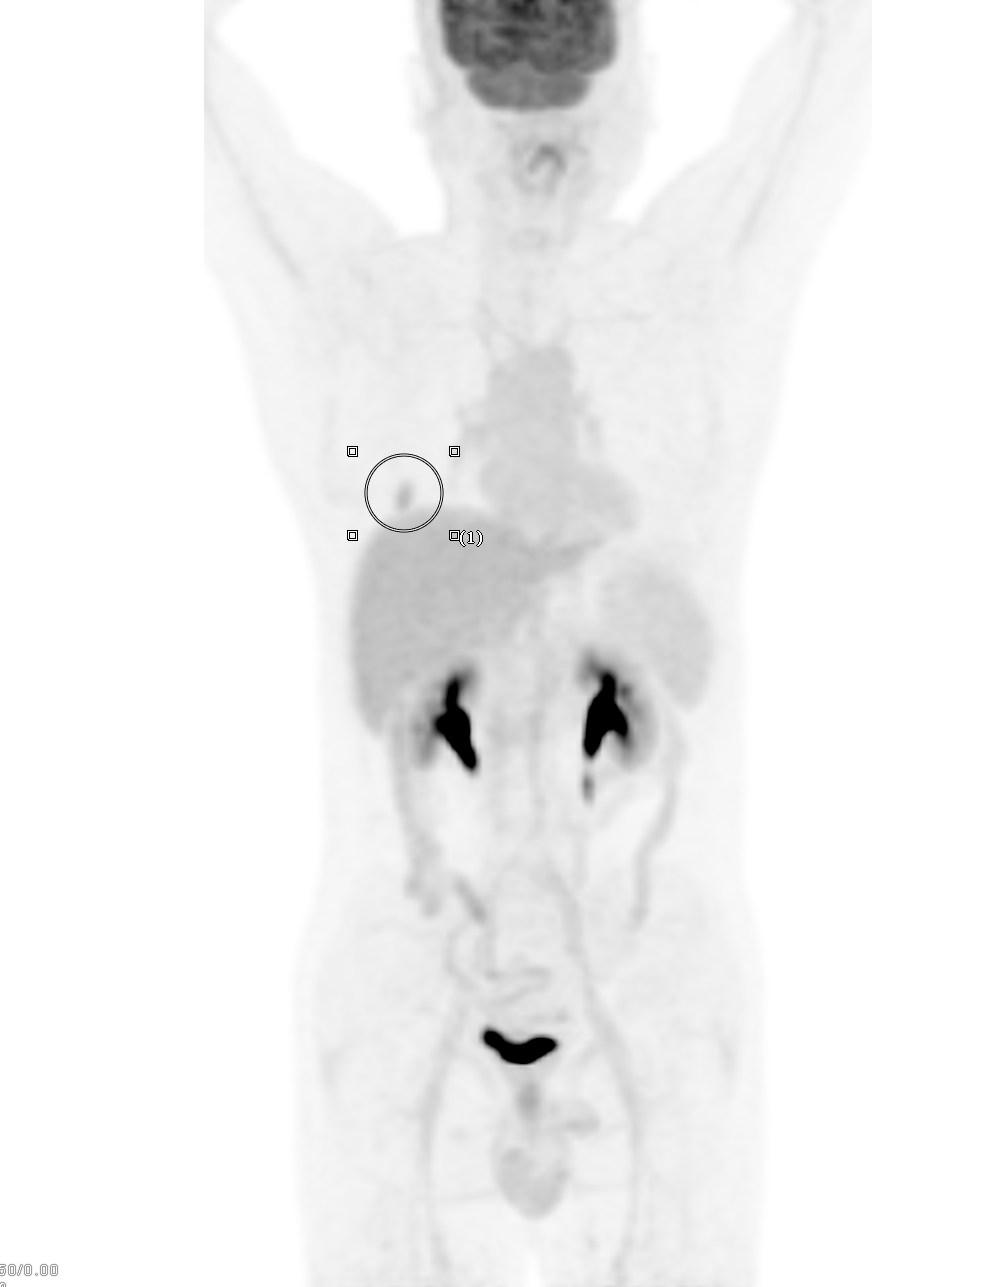

患者1:图1

经常看我科普及所有临床或者影像科医生对这个结节的诊断都没有什么怀疑,病灶大小约2.0cm×1.2cm,实性软组织成分,病灶呈分叶状,周边可见长短不一毛刺,并可见小空洞,相邻胸膜牵拉,全部是恶性征象。单单从CT诊断基本明确。

患者1:图2

另外,薄层CT还提示肺内还发现3个结节,从CT上诊断明确,考虑为纤维增殖灶。